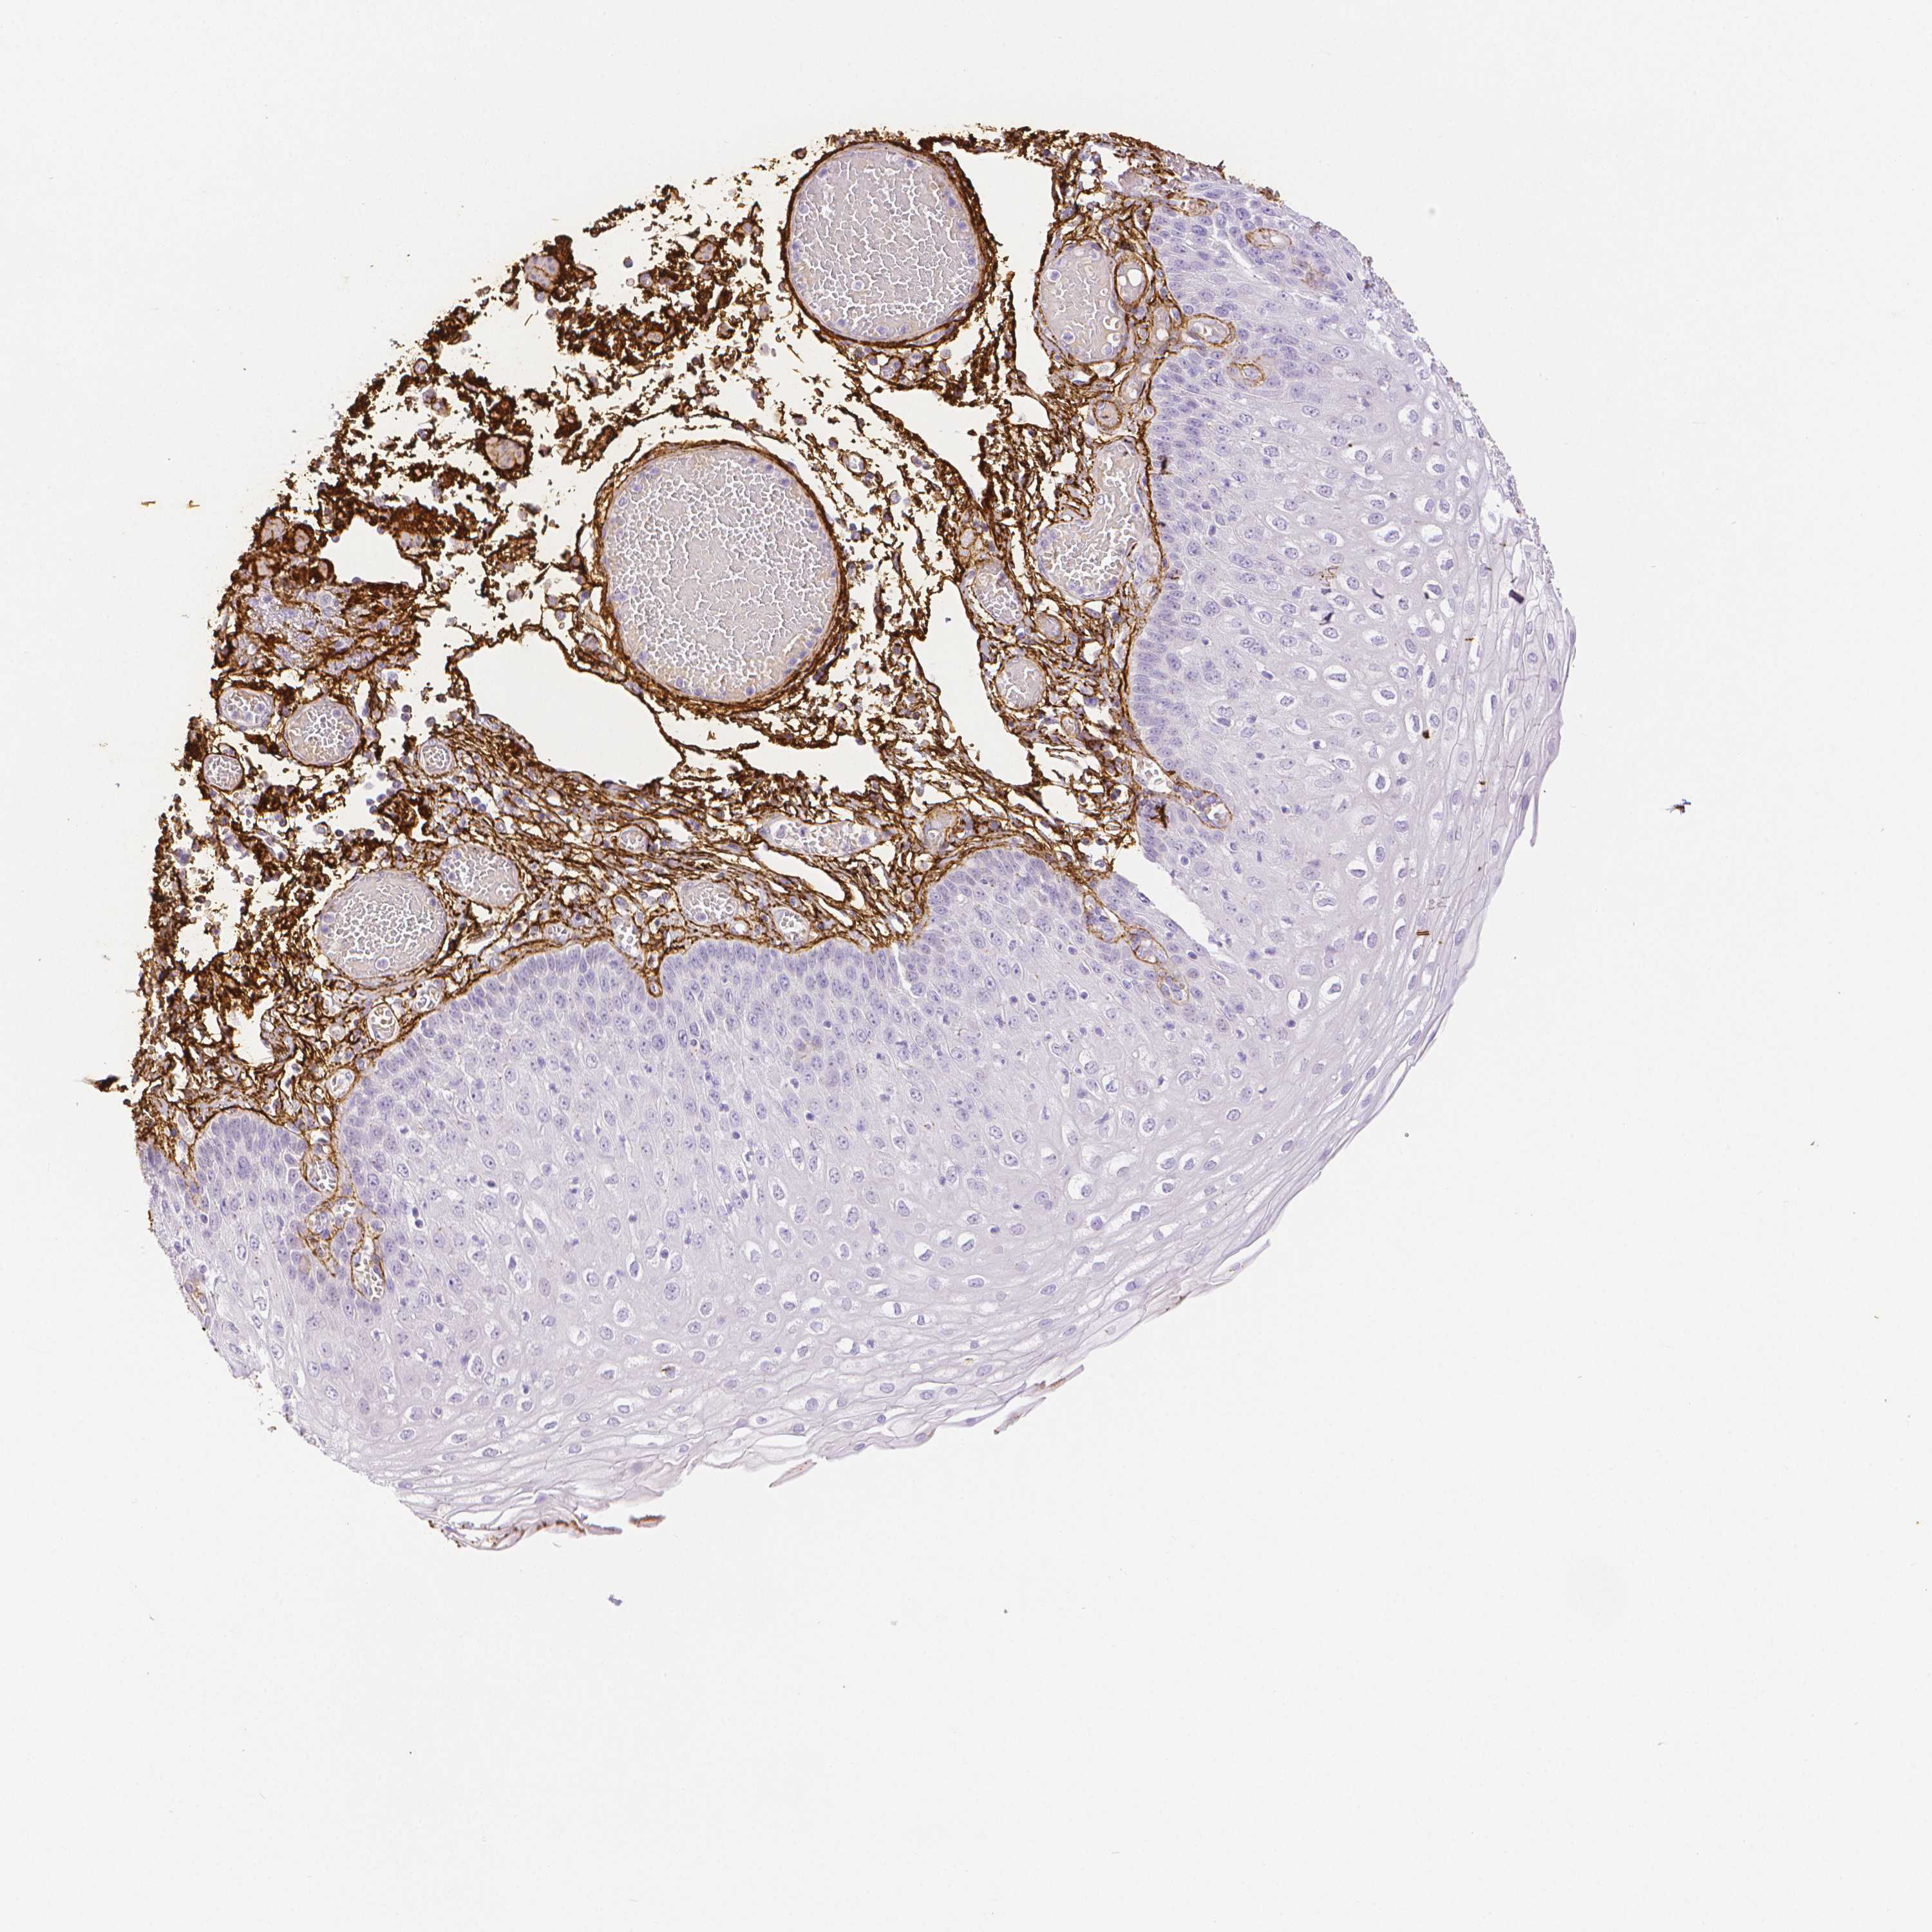

ESOPHAGUS - Antibody stainingi

Antibody staining in the annotated cell types in the current human tissue is reported as not detected, low, medium, or high, based on conventional immunohistochemistry profiling in selected tissues. This score is based on the combination of the staining intensity and fraction of stained cells.

Each image is clickable and will lead to virtual microscopy that enables deeper exploration of all samples and also displays staining intensity scores, fraction scores and subcellular localization as well as patient and tissue information for each sample.

Antibody HPA017759Antibody HPA021057Antibody CAB002670Antibody CAB058696Antibody CAB068188Antibody CAB080202

Squamous epithelial cells Not detectedNot detectedNot detectedNot detectedNot detectedNot detected